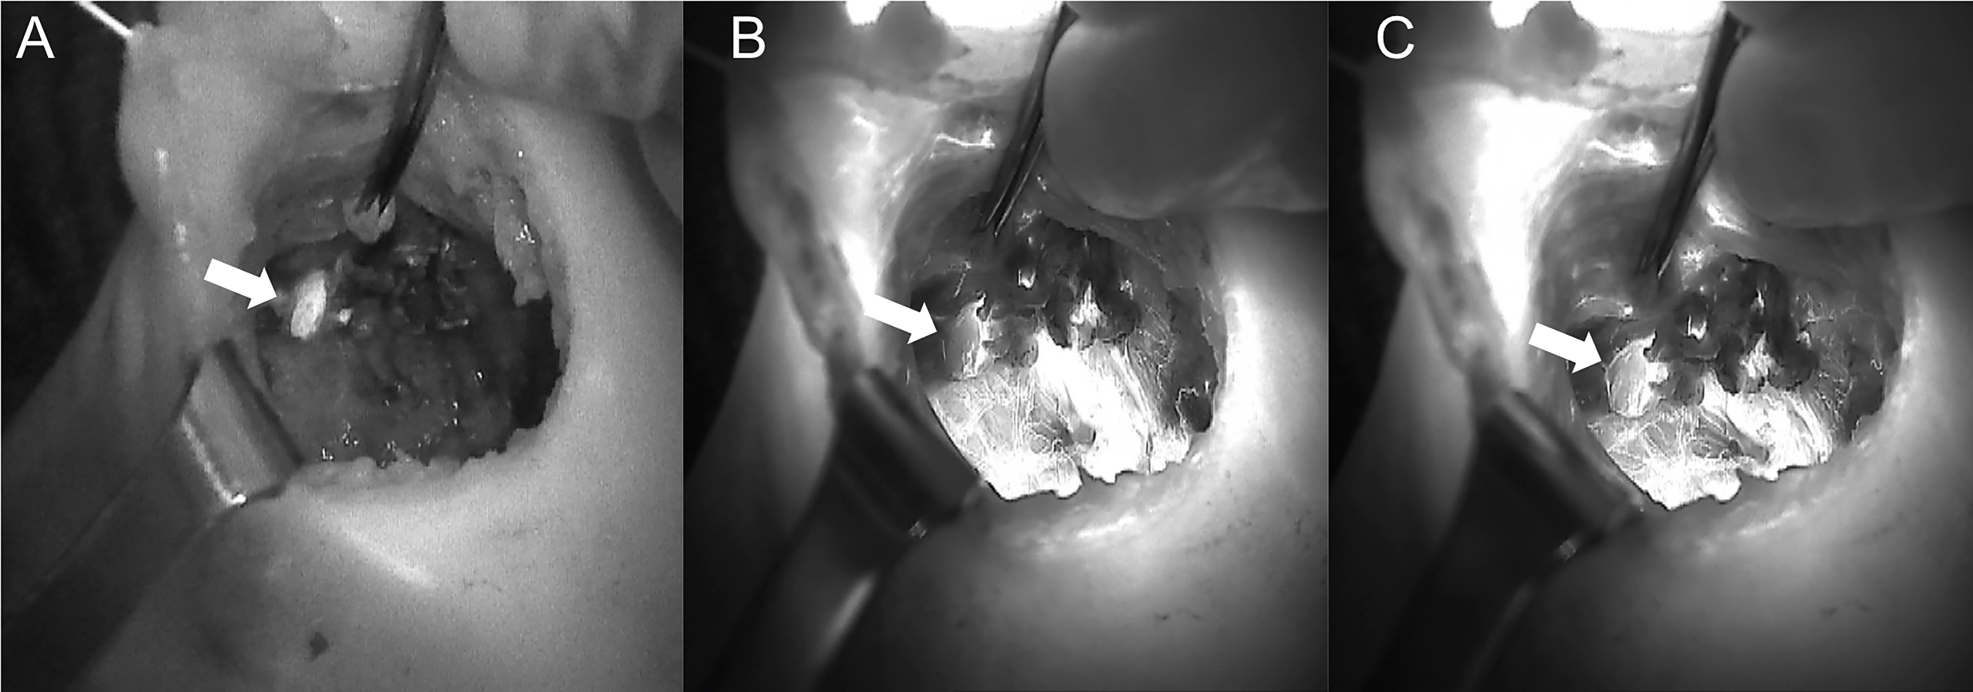

The introduction of NIRAF has vastly improved intraoperative imaging [47, 48]. Many recent studies (Table 2) have demonstrated that the use of NIRAF during thyroid surgery can improve surgical outcomes by facilitating PG identification (Figures 1 –3), which reduces the incidence of postoperative hypoparathyroidism. In particular, Benmilloud et al. showed that NIRAF improved PG identification and helped to reduce the rate of temporary postoperative hypocalcemia, parathyroid autotransplantation, and inadvertent parathyroid resection [48, 66]. In the literature, NIR devices have been shown to facilitate parathyroid gland identification by detecting their AF before conventional, visual recognition by the surgeon, in 37–67% of cases [49]. Additionally, these devices enable the early identification of PGs before surgical dissection, helping to preserve their vasculature [50]. A systematic review and meta-analysis by Barbieri et al. found that NIR fluorescence imaging reduced short and medium-term hypocalcemia compared to conventional surgery [51]. Moreover, NIRAF can detect subcapsular/intrathyroidal PGs or PGs that have been accidentally removed, which can then be resected from the thyroid specimen and auto planted back into the patient (Figures 4 and 5). In addition to the identification of normal PGs, NIRAF can help to identify a pathological PG. Parathyroid adenomas exhibit a more heterogeneous and less intense autofluorescence signature than that of normal PGs (Figure 6), enabling the differentiation between a normally functioning and a pathological PG [52, 53]. Furthermore, the fluorophore is resistant to freezing, heating, and fixing with formalin, meaning that the autofluorescence properties are preserved after gland resection [4, 29, 42, 43].

Three phases of dissection of subcapsular parathyroid (indicated with a white arrow), which was detected using Fluobeam LX near-infrared autofluorescence (NIRAF) imaging. The parathyroid gland (PG) can then be transplanted.